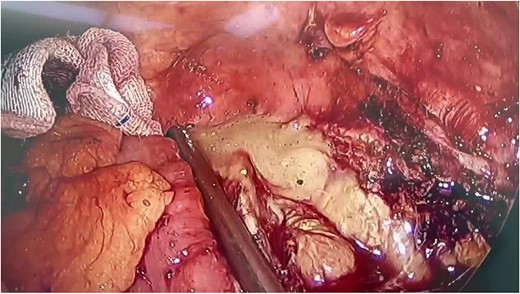

The patient underwent emergent laparoscopic surgery. During the operation, the peritoneum was found to be clean, except for an abscess located behind the lesser omentum. The appendix was buried behind the terminal part of the ileum, making it difficult to recognize due to the loss of its normal shape. The appendiceal wall was scattered in the pus. During the surgical procedure, we gained access to the retroperitoneal abscess by opening the right paracolic gutter, which revealed a significant accumulation of dark yellow pus (Fig. 2). Appendicectomy and necrosectomy were performed in the retroperitoneal space. Necrotic tissue behind the cecum, small intestine, and stomach was removed. Four drainage tubes were placed at the end of the surgery, two in the peritoneum and two in the retroperitoneum. Necrotic tissue was observed in the drainage tubes, particularly in the retroperitoneal ones, during the first 7 days. The amount of necrotic tissue decreased over time, and the peritoneal drains were removed first. After 13 days post-surgery, all drainage tubes were removed. On the 15th day of admission, the patient’s laboratory data improved, and he was discharged from the hospital.

During the operation, a significant accumulation of pus was revealed.